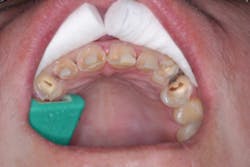

I knew Sarah when she was well and could smile at the world. Then, when the painful loss of a loved one dismantled her life, having no safety net or support, depression set in. Later, substance abuse took over, and eventually Sarah hit rock bottom. Thankfully, a local family took her in, and she is reclaiming her life. But her teeth and smile were devastated (figures 1 and 2).

Wednesday is sedation day in our office, It's one of my favorite days—one patient and all the time I want to care for that one person. Using 3.5x loupes, caries detecting solution, and slow-speed excavation, we teased out massive amounts of decay throughout the arch with complete pulpal communication in teeth Nos. 6, 10, and 11 (figure 4). We were prepared for pulpal involvement and the possibility that multiple teeth might require root canal treatment on the fly. I immediately performed same-day root canals on the three teeth (figure 5).